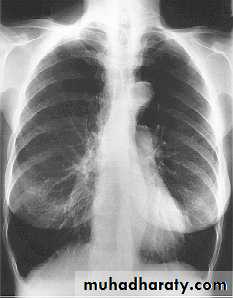

• Chest X-ray

• The presence emphysema can be suspected on routine chest radiography but this is not a sensitive technique for diagnosis.

• Large volume lungs with

• a narrow mediastinum and

• flat diaphragms are the typical appearances. In addition, the presence of bullae and irregular distribution of the lung vasculature may be present.

• In more advanced disease, the presence of pulmonary hypertension may be suspected by the prominence of hilar vasculature. The chest X-ray is not a very good indicator of the severity of disease and will not be able to identify patients with COPD without significant emphysema.

• However, the chest X-ray is useful to look for complications during acute exacerbations and to exclude other pathology such as lung cancer.